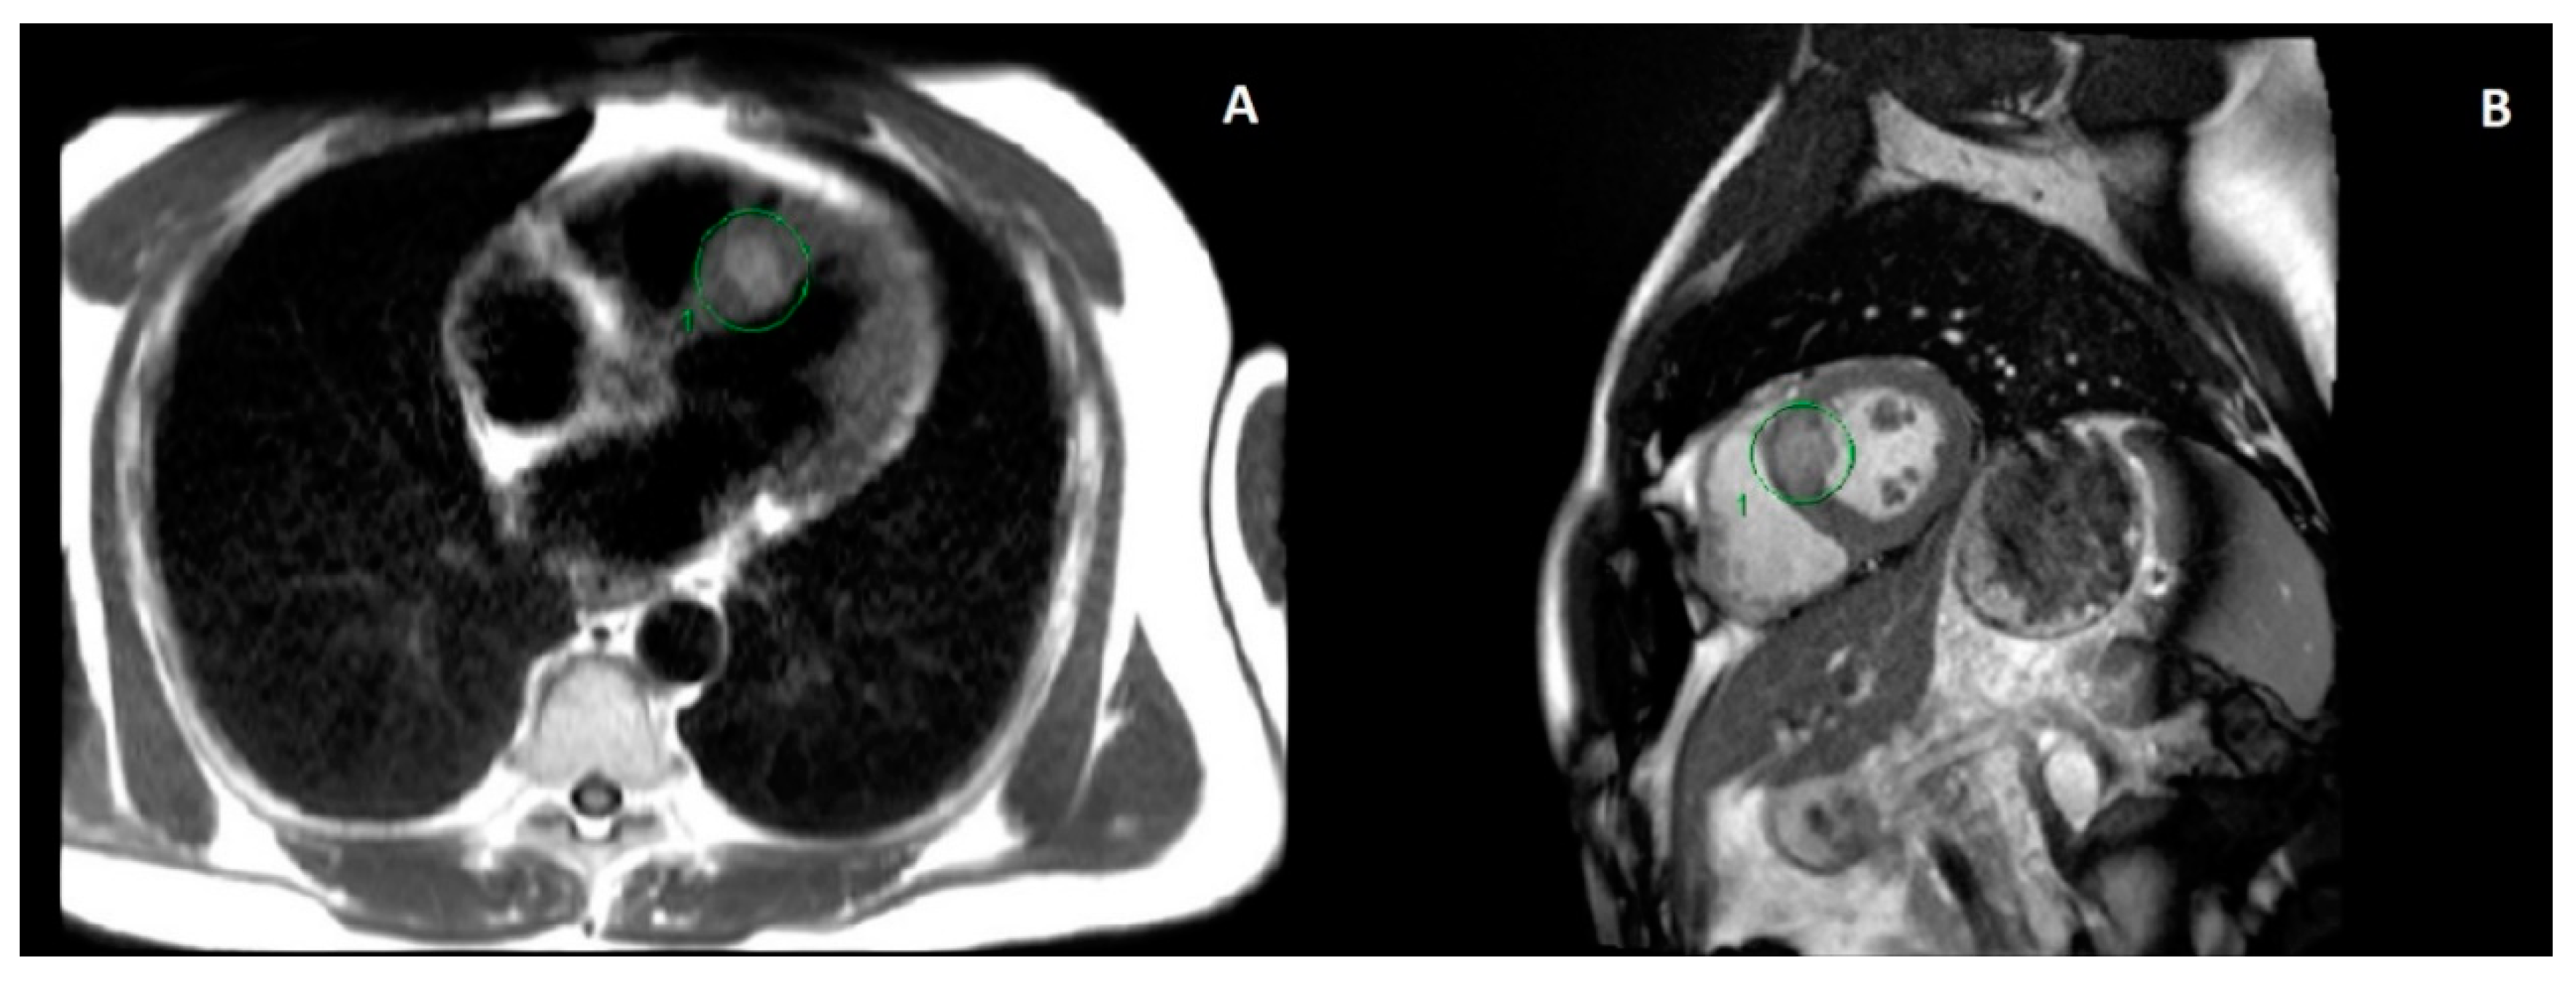

Overall, the patient tolerated his treatment course well. During his treatment, he had one episode of chest pain that self-resolved without physician intervention (grade 1 cardiac pain, by Common Terminology Criteria for Adverse Events (CTCAE) v5.0), as well as some mild dyspnoea on exertion (grade 1 dyspnoea by CTCAE v5.0). Two weeks later, he had an ECG showing no significant abnormalities. Six weeks after treatment, an echocardiogram showed a left ventricular ejection fraction (LVEF) of 63% and no visualised myocardial lesion. An echocardiogram done five years prior showed a LVEF of 53%, and no myocardial lesion was seen. An MRI performed two months after treatment (Figure 3) showed stability of his cardiac lesion, although no contrast was given for his MRI scan due to concerns of renal dysfunction at the time.

Figure 3. MRI of the thorax and upper abdomen done three months after radiation treatment, showing stability of the metastatic myocardial lesion (circled). No gadolinium contrast was used for this scan, as the patient had an acute kidney injury at the time. Representative axial (A) and sagittal (B) images are shown on the left and right, respectively.

In our case, the patient did have mild chest pain and dyspnoea on exertion, although these self-resolved without intervention. There was improvement of the ECG findings after beta blocker therapy was started in hospital, and this continued for the remainder of the patient’s life. The troponin level prior to SBRT was normal and was not repeated after SBRT. An echocardiogram after SBRT did not reveal the lesion. His cardiac-gated MRI done prior to and after SBRT showed stability of the lesion. CT imaging of the chest was also done before and after SBRT, but these did not show the lesion as clearly as the cardiac-gated MRI.